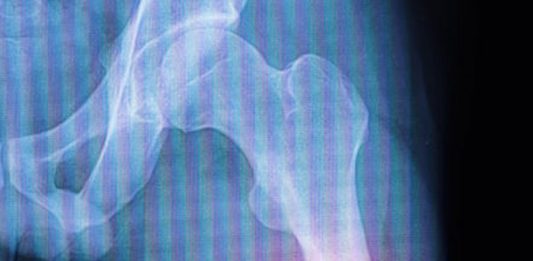

Femur şaft kırıkları, femur kemiğinin orta kısmında meydana gelen ciddi yaralanmalardır. Bu tür kırıklar genellikle motorlu araç kazaları veya düşme gibi yüksek enerjili travmalar sonucu ortaya çıkar. Yaşlı bireylerde, düşük enerjili travmalar bile femur şaft kırıklarına yol açabilir, çünkü kemik yoğunluğu yaşla birlikte azalır. Femur, vücuttaki en uzun ve en güçlü kemiktir ve ağırlık taşıma … Femur Şaft Kırıkları okumayı sürdür